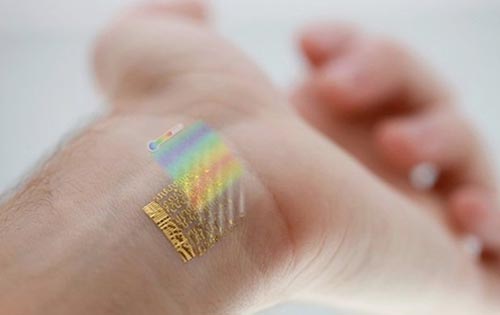

Ερευνητές από το πανεπιστήμιο του Ιλινόις έχουν κατασκευάσει έναν αισθητήρα, ο οποίος μπορεί να προσκολληθεί επάνω στο δέρμα και να παρακολουθεί τη θερμοκρασία, τα επίπεδα ενυδάτωσης και τις αλλαγές στο κυκλοφορικό σύστημα του ατόμου. Ο εύκαμπτος αυτός αισθητήρας είναι κατασκευασμένος από χρυσό και πυρίτιο και τοποθετείται στα άκρα του ατόμου με μια ελαφριά κόλλα, επάνω στο δέρμα.

Επίσης, μια ομάδα ερευνητών από το πανεπιστήμιο Σαν Ντιέγκο της Καλιφόρνια, έχει αναπτύξει έναν αισθητήρα, που μοιάζει σαν ένα προσωρινό τατουάζ, χάρη στον οποίο μπορούν να μετρήσουν τη σωματική προσπάθεια που καταβάλλει ένας αθλητής. Ο αισθητήρας ελέγχει τις χημικές ουσίες που περιέχονται στον ιδρώτα του ατόμου, υπολογίζοντας την ύπαρξη στοχείων-«κλειδιά», όπως το γαλακτικό οξύ.